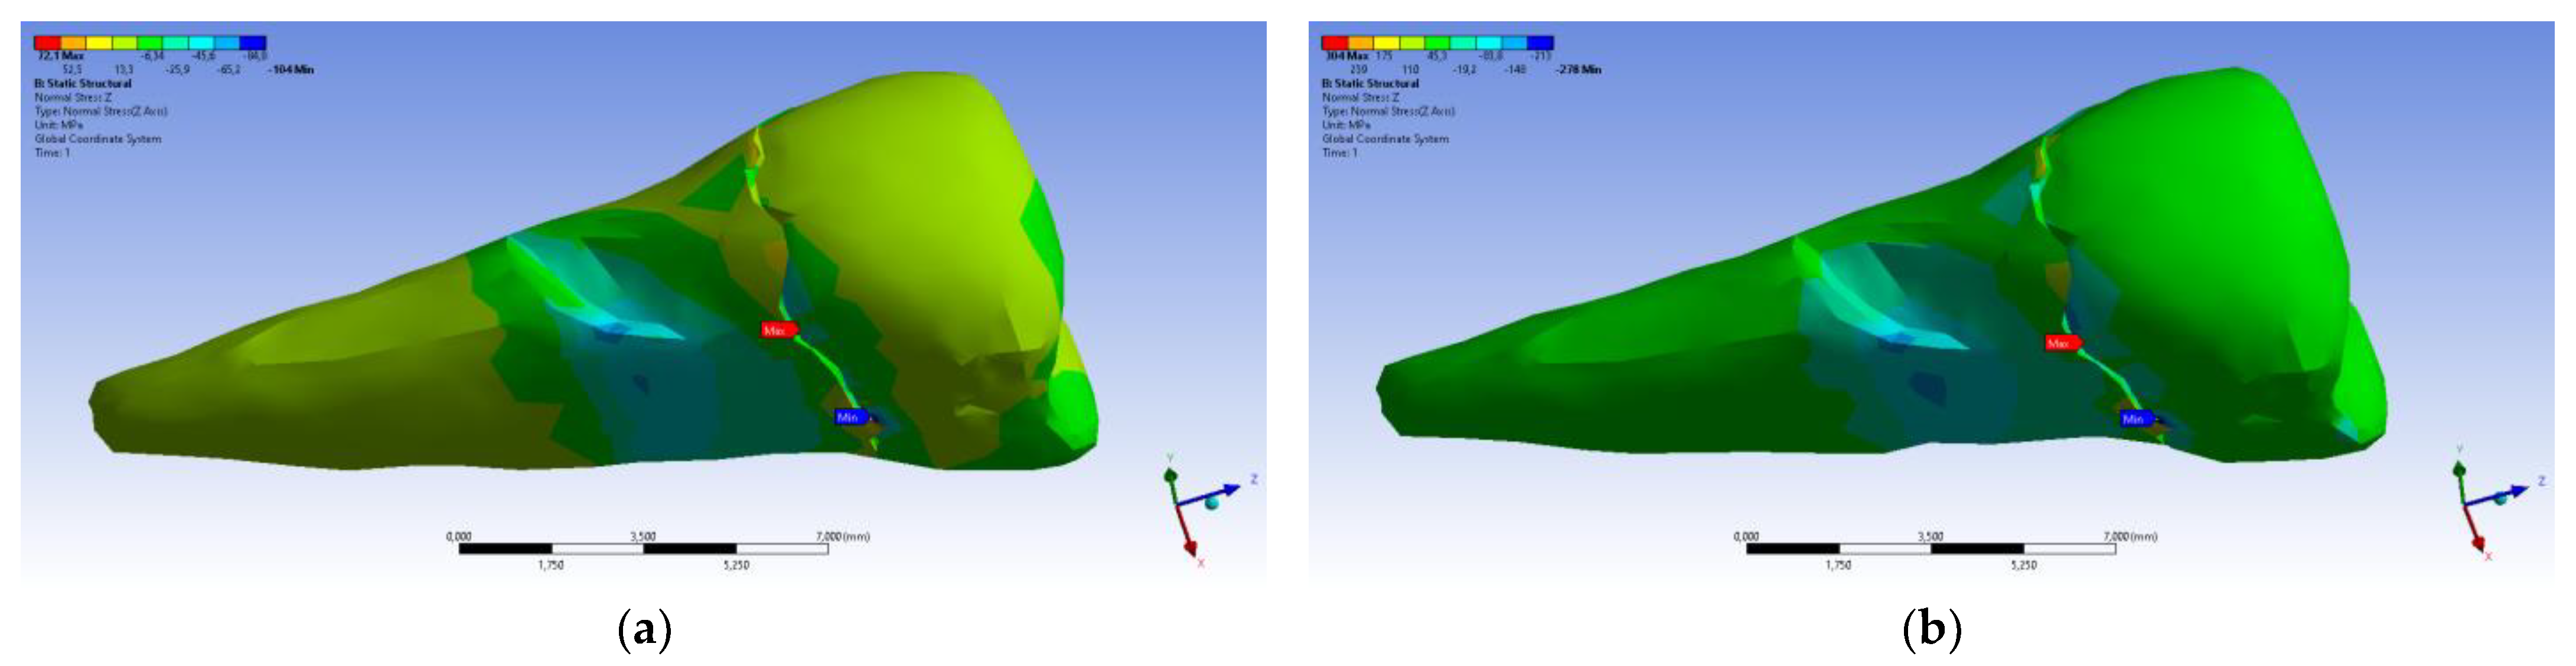

| Total Deformation | Deformation in X Direction | Deformation in Y Direction | Deformation in Z Direction | Equivalent Stress | Normal Stress X | Normal Stress Y | Normal Stress Z | Maximum Main Stress | Minimum Main Stress | Tangential Stress XY | Tangential Stress YZ | Tangential Stress XZ | |

|---|---|---|---|---|---|---|---|---|---|---|---|---|---|

| Minimum | 0 mm | −4.24 × 10−3 mm | −2.52 × 10−2 mm | −1.56 × 10−2 mm | 1.01 × 10−6 MPa | −35.6 MPa | −57.1 MPa | −104 MPa | −15.2 MPa | −152 MPa | −43.7 MPa | −39.6 MPa | −56.3 MPa |

| Maximum | 2.77 × 10−2 mm | 3.57 × 10−3 mm | 6.98 × 10−4 mm | 4.78 × 10−3 mm | 248 MPa | 61.5 MPa | 177 MPa | 72.2 MPa | 195 MPa | 21.4 MPa | 44.2 MPa | 117 MPa | 22.2 MPa |

| Minim. in | Cementum | Cementum | Enamel | Enamel | Cementum | Cementum | Enamel | Enamel | Enamel | Cementum | Enamel | Enamel | Cementum |

| Maxim. in | Enamel | Enamel | Cementum | Enamel | Cementum | Enamel | Enamel | Enamel | Enamel | Enamel | Cementum | Cementum | Cementum |

| Total Deformation | Deformation in X Direction | Deformation in Y Direction | Deformation in Z Direction | Equivalent Stress | Normal Stress X | Normal Stress Y | Normal Stress Z | Maximum Main Stress | Minimum Main Stress | Tangential Stress XY | Tangential Stress YZ | Tangential Stress XZ | |

|---|---|---|---|---|---|---|---|---|---|---|---|---|---|

| Minimum | 0 mm | −6.1 × 10−3 mm | −9.02 × 10−2 mm | −3.99 × 10−2 mm | 1.02 × 10−6 MPa | −112 MPa | −199 MPa | −278 MPa | −65.5 MPa | −470 MPa | −148 MPa | −176 MPa | −178 MPa |

| Maximum | 9.28 × 10−2 mm | 1.83 × 10−2 mm | 1.38 × 10−3 mm | 3.12 × 10−2 mm | 780 MPa | 61.5 MPa | 649 MPa | 304 MPa | 704 MPa | 73.8 MPa | 134 MPa | 370 MPa | 78.6 MPa |

| Minim. in | Cementum | Cementum | Enamel | Enamel | Cementum | Cementum | Enamel | Enamel | Enamel | Cementum | Enamel | Enamel | Cementum |

| Maxim. in | Enamel | Enamel | Cementum | Enamel | Cementum | Enamel | Enamel | Enamel | Enamel | Enamel | Cementum | Cementum | Cementum |